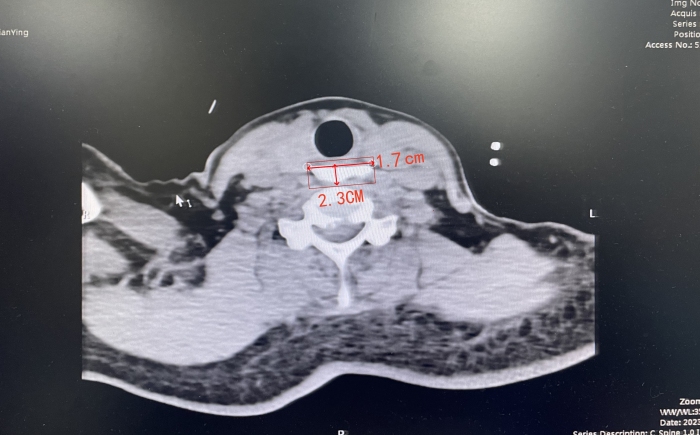

近日,中南大学湘雅二医院桂林医院内镜中心接诊了一名面容异常痛苦的患者。患者刘先生在家吃饭时不慎将一块骨头误吞卡在食管,家属紧急将其送往医院。医师检查后发现,异物卡在了食管入口的第一个狭窄处,且两端尖锐、体积较大,异物长达2.3厘米,宽至1.7厘米,稍有不慎,患者随时会有危险。

患者到院后,消化内科、内镜中心医师庾艳军了解刘先生的情况后,立即安排其进行颈部CT检查,以明确异物所在部位及异物与周边组织的关系。从CT判断,继续耽搁下去可能会给患者带来更大风险,骨头移位可能造成食道穿孔或者骨头移位后卡在临近主动脉的第二狭窄处,后果将更为严重!庾艳军立刻协调安排,预估手术风险及难度,进行术前模拟和讨论,以最快速度完善相关术前准备,确保以最短时间、最小损伤完成此次手术治疗。